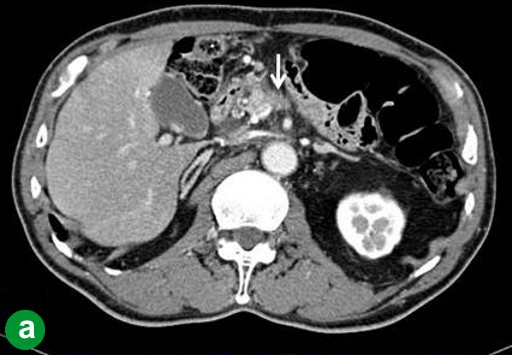

In January 2008, the patient complained of hydrodipsia and polyuria, and was diagnosed with diabetes mellitus. An abdominal CT scan revealed a 3 cm tumor in the tail of the pancreas (Figure 2a). Tumor marker (CEA and carbohydrate antigen (CA) 19-9) levels were within the reference limits, and had been throughout previous monitoring. Recurrence was confirmed using FDG-PET at 84 months after the initial operation. The FDG-PET hot spot corresponded with the tumor location shown by the CT scan (Figure 2b). The patient underwent surgery in June 2008. An intra-operative pathological examination indicated an adenocarcinoma of the remnant pancreas. A remnant distal pancreatectomy with a splenectomy was performed. The histopathological findings for the second neoplasm were similar to those of the initial lesion (Figure 2c). Carcinoma cells had invaded vessels, lymph ducts and neurons, and there were lymph node metastases (T3N1M0; R0; pathological stage: IIB). The patient was alive at 10 months after the second operation without any recurrence.

|

Figure 2. Case#1: second operation. a. A tumor approximately 3 cm in diameter was detected in the pancreatic tail on abdominal CT. b. A hot spot in FDG-PET corresponded to the tumor site on CT. c. A well- or moderately-differentiated tubular adenocarcinoma similar to the initial pancreatic cancer was detected. Mild atypical cells with a slightly swollen nucleus formed an irregular ductal structure and invaded the parenchyma. (H&E stain, x100). |